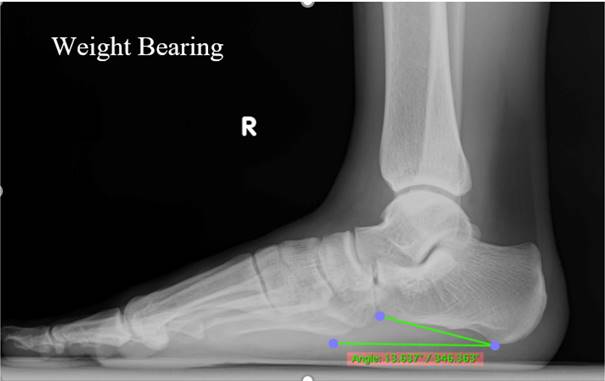

Figure 5

Lateral radiograph shows the calcaneal inclination angle.

Radiography

Weight-bearing foot and ankle lateral projection radiographs remain the gold standard for diagnosing AAFD.[14] The X-ray machine unit of the DRGEM Stationary X-ray System GXR-C52SD was used for the examination. Standing lateral views of the foot were obtained for all athletes (Figure 4). All radiographs were obtained in a weight-bearing position using a standardized technique with the same digital radiography system. The athletes were advised to let passive movement go through their ankle and foot arch to ensure no manipulations in the measurements. The digital X-ray detector (film) and X-ray tube (source) were 35-40 inches apart in both the lateral views of the foot. The CIA is one of the most common measurements to diagnose flatfoot deformity (Figure 5). The CIA was measured by the angle between the line, parallel to the plantar calcaneal surface, and the horizontal plane. The plantar calcaneal surface is measured by the most inferior portion of the calcaneal tuberosity and the most distal and inferior point of the calcaneus at the calcaneocuboid joint.[23] Alignment angles (degrees) <18° were categorized as pes planus.[5, 24, 25]